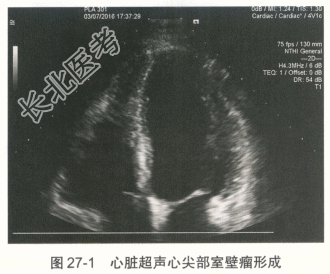

患者男性,41岁,2016年2月20日晚间无明显诱因出现发热,体温最高38.0℃,伴轻微胸闷、憋气、头晕、头痛、恶心,偶有呕吐及四肢酸痛,无胸痛及肩背部放射痛,自行服用对乙酰氨基酚1片后症状不缓解。21日晨起体温38.5℃,伴全身乏力,至当地医院行胸片检查未见明显异常,行血常规检查提示白细胞、中性粒细胞偏高(具体数值不详),考虑炎性病变,回当地诊所继续输液治疗(药名及剂量不详),效果欠佳。22日上午患者出现胸闷、憋气、四肢无力,伴恶心,无呕吐,输液期间症状反复发作,逐渐加重。23日2:00胸闷、憋气明显,突发意识丧失,急呼120送至保定市第一中心医院,检查结果示:CK-MB39.6ng/ml↑,肌红蛋白431.0ng/ml↑,肌钙蛋白18.4ng/ml↑,BNP536.00pg/ml↑,D-二聚体0.7μg/ml↑,ALT615.00U/L↑,AST781.00U/L↑,肌酐204.9μmol/L↑,当地医院诊断"重型心肌炎",给予抗炎、抗病毒治疗,静脉泵入异丙肾上腺素、多巴胺及甲泼尼龙,体温逐渐回落至正常,但胸闷、憋气、乏力等症状无缓解。当晚17:00左右送至我院急诊科,转运过程中胸闷、憋气症状进行性加重。心电图示:三度房室传导阻滞。心脏超声:左室整体功能减退,二、三尖瓣轻度反流,少量心包积液,未见节段性室壁运动障碍。我院给予异丙肾上腺素、甲泼尼龙冲击、盐酸多巴胺等治疗,给予急诊临时起搏器。随后收入我科,心电图提示加速性室性自主心律。吸烟史10余年,约20支/天,无饮酒史,家族无遗传病史。 入科后因临时起搏导管感知不良,更换临时起搏器期间患者突然出现意识丧失,伴抽搐,持续约2分钟后患者意识逐渐恢复,但躁动明显,伴呼吸困难,氧饱和度维持在85%左右,行气管插管术,吸出大量粉红色泡沫样痰,给予托拉塞米40mg静脉推注,呼吸机持续辅助呼吸,氧饱和度逐渐回升至100%。入科后查体:血压71/49mmHg,心率55次/分,双肺大量湿啰音,心音低钝,未闻及明显杂音。检查:CK-MB、肌红蛋白、肌钙蛋白、D-二聚体、ALT、AST、γ-GGT、肌酐均升高,BNP>35000pg/ml,血常规示:白细胞计数和中性粒细胞升高。2月23日肺部CT提示双侧肺水肿,双侧胸腔积液。经应用激素及其他辅助药物治疗后,患者病情逐渐稳定,临床症状及化验检查.心电图、胸部CT均明显改善。 患者3月7日复查超声心动图提示心尖部室壁瘤形成,不除外心肌梗死所致(图27-1)。因而进一步行冠脉CT及心脏磁共振。冠脉CT未见明显冠状动脉狭窄。心脏磁共振:①左室心尖节段性延迟强化并反向运动;②左侧-侧壁心肌弥漫水肿并延迟强化,明确有室壁瘤形成(图27-2)。3月7日EBV-DNA定量检测阳性,C-反应蛋白6.28mg/dl。